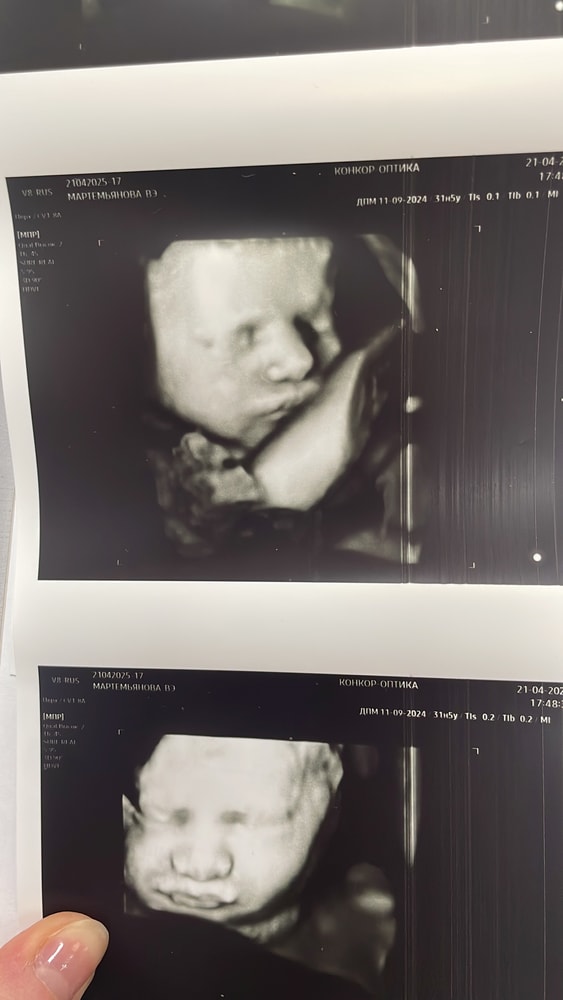

Я пошла на 9м😅 Не хотела фоткаться , пряталась 😅 Изображение